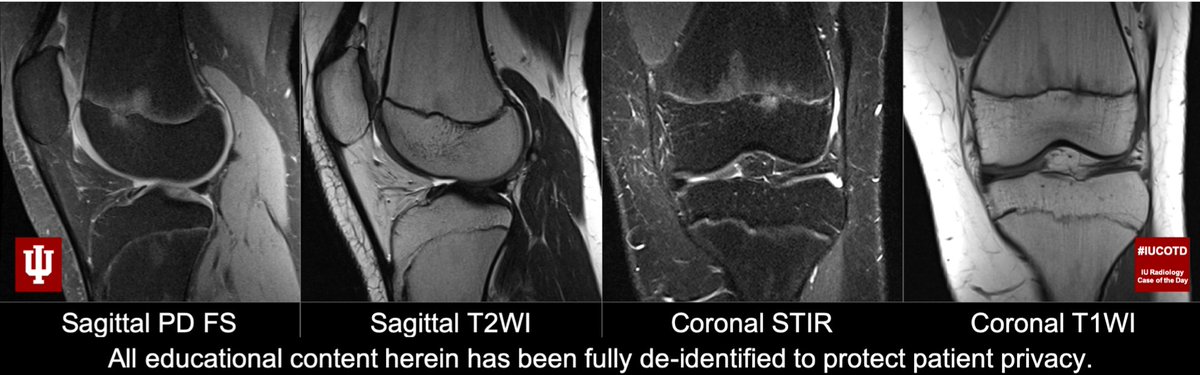

#IUCOTD #191 ANSWER: Cyclops lesion! Thx Drs.@TimTsaiMD & Maertz for the case!#FOAMRad#RadRes#MedEd#MSKRad#Radiology Learn more: https://youtu.be/zURxArNLu70@IURadiology#IUCOTD#YouTube: https://bit.ly/2EXkWnX pic.twitter.com/iQm0a7t1rn